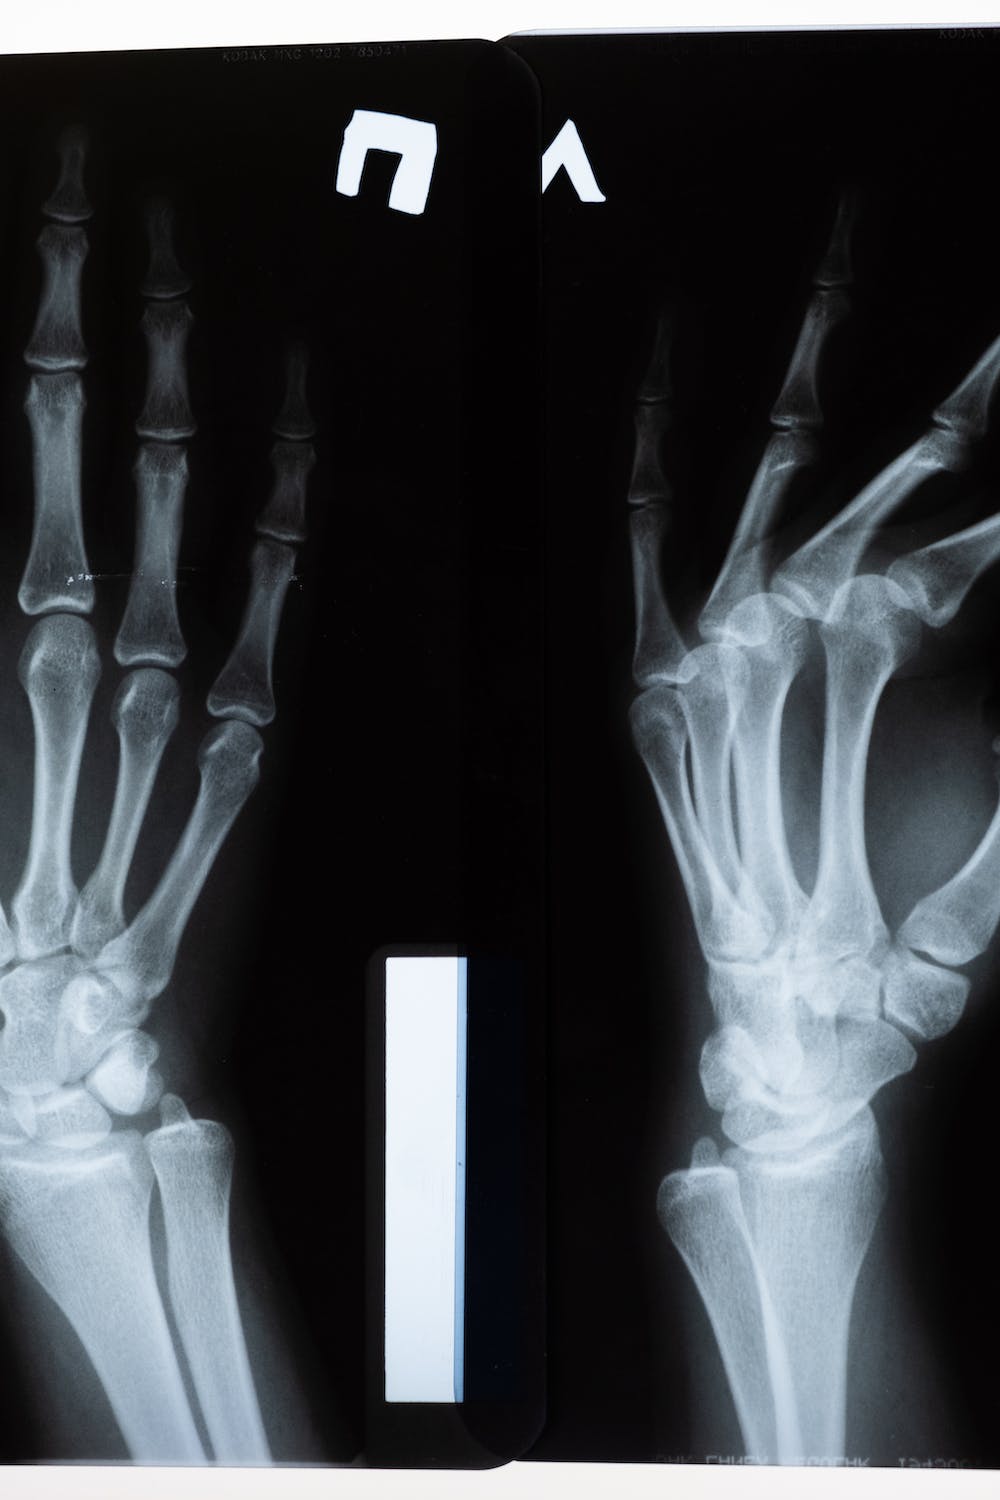

뼈의 강도가 약해져서 골절이 일어날 가능성이 높은 상태로 골다공이란 뼛속에 구멍이 많이 생긴다는 뜻이며, 골다공증은 뼈의 대표적인 미네랄인 칼슘과 인이 감소함에 따라 뼈의 양이 줄어들어 뼈가 얇아지고 약해져 잘 부러지는 질환을 의미합니다.

뼈의 특성상 초기에는 특별한 증상이 나타나지 않으나 초기 증상 중 하나는 척추뼈가 약해져서 척추가 후만 변형되거나 압박되어 신장이 줄어드는 것입니다.

또한 골절의 위험이 높아지게 되며 심할 경우 허리를 구부리거나 기침을 하는 등 일상생활 중에도 뼈가 쉽게 부러질 수 있습니다.

50~70세 여성의 골절은 주로 손목에서 먼저 발생하는 경우가 많으며 70대 환자들의 경우 고관절 및 척추의 골절이 흔하게 발생하게 됩니다.